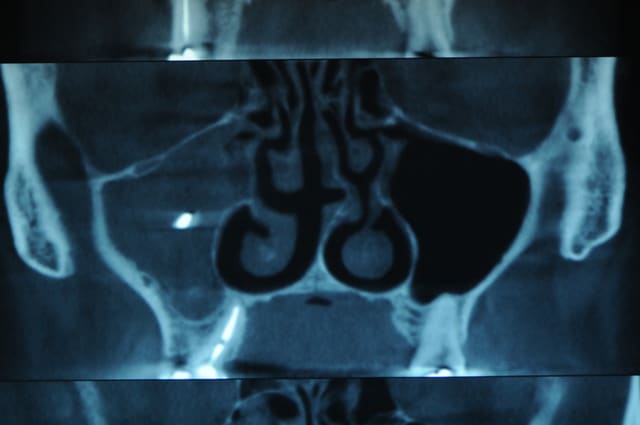

par contre, le patient se plein encore de douleurs et je lui fait un cone beam .

y a pas un truc qui vous chagrine ?

Je vais faire l'idiot et te dire : "mais tu nous a mis le CB d'AVANT l'intervention de l'ORL !?".

il a traité l'autre sinus (le sinus déjà sain) :-)

Que pensez-vous de cette bouse très radio-opaque dans le sinus maxillaire gauche ?

Pâte à canaux (un pot entier) ?

Noyau de pêche ?

Boulette de shit ?

> Que pensez-vous de cette bouse très radio-opaque dans le sinus maxillaire gauche

> ?

> Pâte à canaux (un pot entier) ?

> Noyau de pêche ?

> Boulette de shit

Comblement de sinus au MTA par voie endocanalaire !

Vu la quantité, on comprends qu'il a les moyens ton patient !